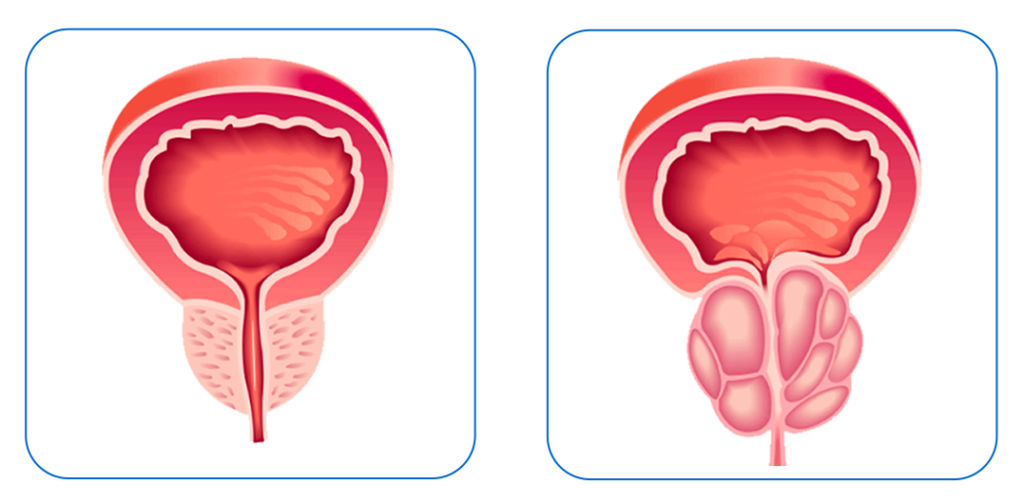

Compreendem as diversas técnicas disponíveis no tratamento cirúrgico da hiperplasia prostática benigna e do câncer da próstata.

Compreendem as diversas técnicas disponíveis no tratamento cirúrgico da hiperplasia prostática benigna e do câncer da próstata.

Hiperplasia prostática e a hiperatividade vesical.

Transtornos miccionais podem ser causados por condições como a hiperplasia prostática benigna(HPB) e a hiperatividade vesical.

A HPB caracteriza-se pelo aumento volumétrico da próstata decorrente do envelhecimento do homem. Anatomicamente a próstata encontra-se logo após a bexiga e envolve a uretra. Desta forma, esse inchaço natural pode causar estreitamento do canal urinário e sintomas de obstrução logo a baixo da bexiga. Na tentativa de vencer essa obstrução, a bexiga aumenta sua força de contração, gerando, ao longo do tempo uma hipertrofia (espessamento) da parede da bexiga. Esse processo pode eventualmente comprometer a capacidade da bexiga de se contrair adequadamente.

Os tratamentos para se evitar e para corrigir essas condições envolvem uso de medicamentos e em muitos casos, intervenções cirúrgicas, como por exemplo os procedimentos endoscópicos (RTU da próstata , Holep), cirurgias laparoscopicas, robóticas e cirurgias abertas.